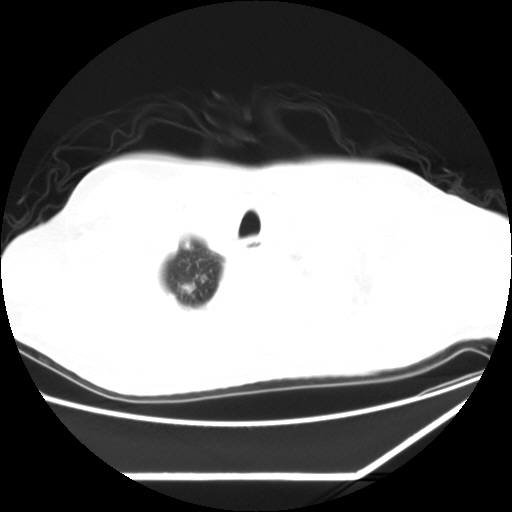

男,57,畏寒,发热

双肺多发结节样病灶,部分内见透光区,纵隔内见淋巴结肿大。结核临床如有畏寒,高热,白细胞增高首先考虑迁徙性肺脓肿(多是金黄色葡萄球菌感染)。

注意除外转移瘤。